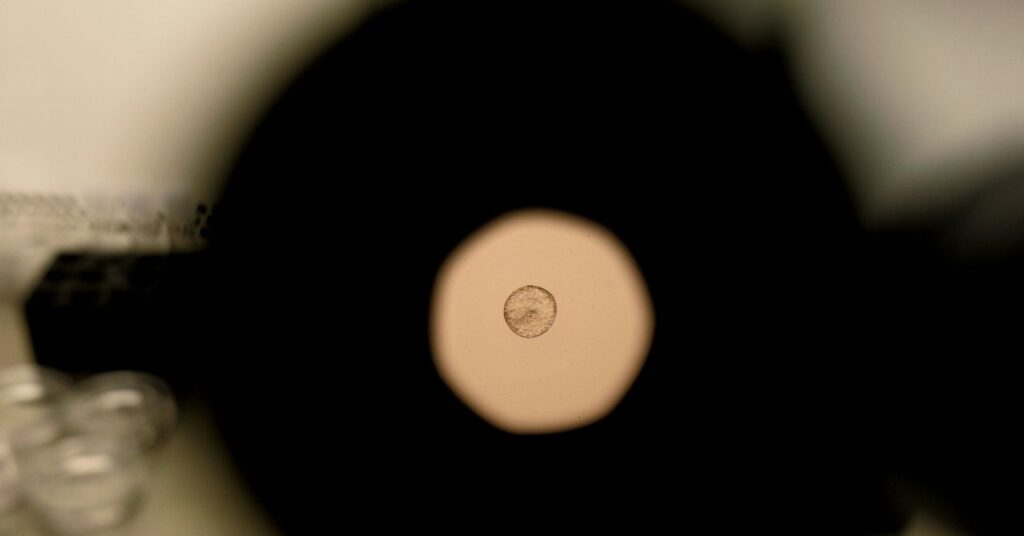

Time-lapse video of the implantation process of a mouse embryo (left) and a human embryo (right).

The human embryos used in this research were provided by Dexeus Mujer Barcelona, a women’s health clinic that specializes in obstetrics, gynecology, and reproductive medicine. “Our work consisted of providing technical advice and rigorously selecting the human embryos donated for research, ensuring they met the ideal conditions for the project,” said Miquel Solé, director of the Dexeus Mujer Cryopreservation Laboratory.